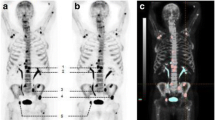

The MAR could be quantified in 8 of 12 biopsies. Three of the remaining four biopsies did not reveal any tetracycline labelling, and the fourth biopsy only revealed single-layer labels. In the evaluable eight biopsies, we found a significant correlation between MAR and 18F-uptake (SUVA50%) (r = 0.80, p = 0.017; Fig. 1). When considering the absence of tetracycline labelling as a lack of BF and thereby a MAR of 0, the correlation coefficient was r = 0.65 (n = 11, p = 0.029). An example of MAR and 18F-fluoride-PET-CT in an individual patient is depicted in Fig. 2.

18F-fluoride-PET-CT and MAR (patient BBR01). a 18F-fluoride-PET before and after treatment is shown. It is illustrated that there is a large variety in 18F-uptake within the patient (range 7.34 to 11.34). After treatment, an increase in 18F-uptake in almost all lesions is seen, again with pronounced intra-individual heterogeneity (range 12.50 to 17.49). b CT and 18F-fluoride-PET of the iliac crest are shown. It is illustrated that the increase in 18F-uptake (11.34 to 13.09) after treatment at the site of the biopsy (red arrow) correlates with a decrease in extramedullary plasmacytoma and increase in osteosclerosis. c The biopsy was taken of the right iliac crest (red arrow in panel a and b). The increase in 18F-uptake (11.34 to 13.09) at this site is reflected by an increase in MAR (1.04 to 1.26). The double layers are pointed by white arrows

Based on conventional imaging, we identified 28 MM bone lesions in the five patients who completed therapy. There was a wide range in 18F-uptake (SUVA50%) before treatment 4.42 to 37.92. In addition, there was a pronounced intra-individual variation as well (minimum range 4.00, BBR01; maximum range 31.18, BBR05) (Table 1).

Similar to before treatment, there was a wide range in 18F-uptake (SUVA50%) after treatment (2.71–37.67; median 11.84). Treatment did not affect 18F-uptake, when considering the median 18F-uptake of all involved lesions before and after treatment (11.74 vs 11.84, p = 0.61). However, a detailed analysis of individual patients revealed that the difference in 18F-uptake before and after treatment not only varied between patients (from −2.20 to 4.53 (median 0.48)) (Fig. 3, Table 1) but also between different lesions within the same patient. For example, in BBR04, 18F-uptake in the posterior iliac crest increased from 5.86 to 10.6 (ratio 1.81), with a concomitant increase in MAR from 0 to 1.37, while the BF in the MM-related bone lesions did not improve (ratios 0.77–1.02) (Fig. 3). In only one patient (BBR01), a homogeneous, statistically significant increase in 18F-uptake was shown due to treatment (7.34–11.34 before and 12.50–17.49 after treatment; p = 0.043) (Fig. 3).